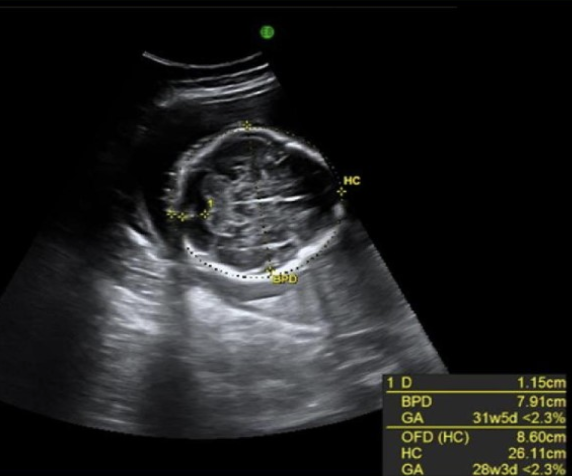

a pregnant pt w/recent acute onset of hypertension, nausea, vomit. she has no pain, cramping, or vaginal bleeding.

.

a prior US exam at 6w shows the pregnancy should now be 17w6d GA.

what maternal serum level is abn elevated

a) acetylcholinesterase

b) bHCG

c) AFP

d) inhibin A